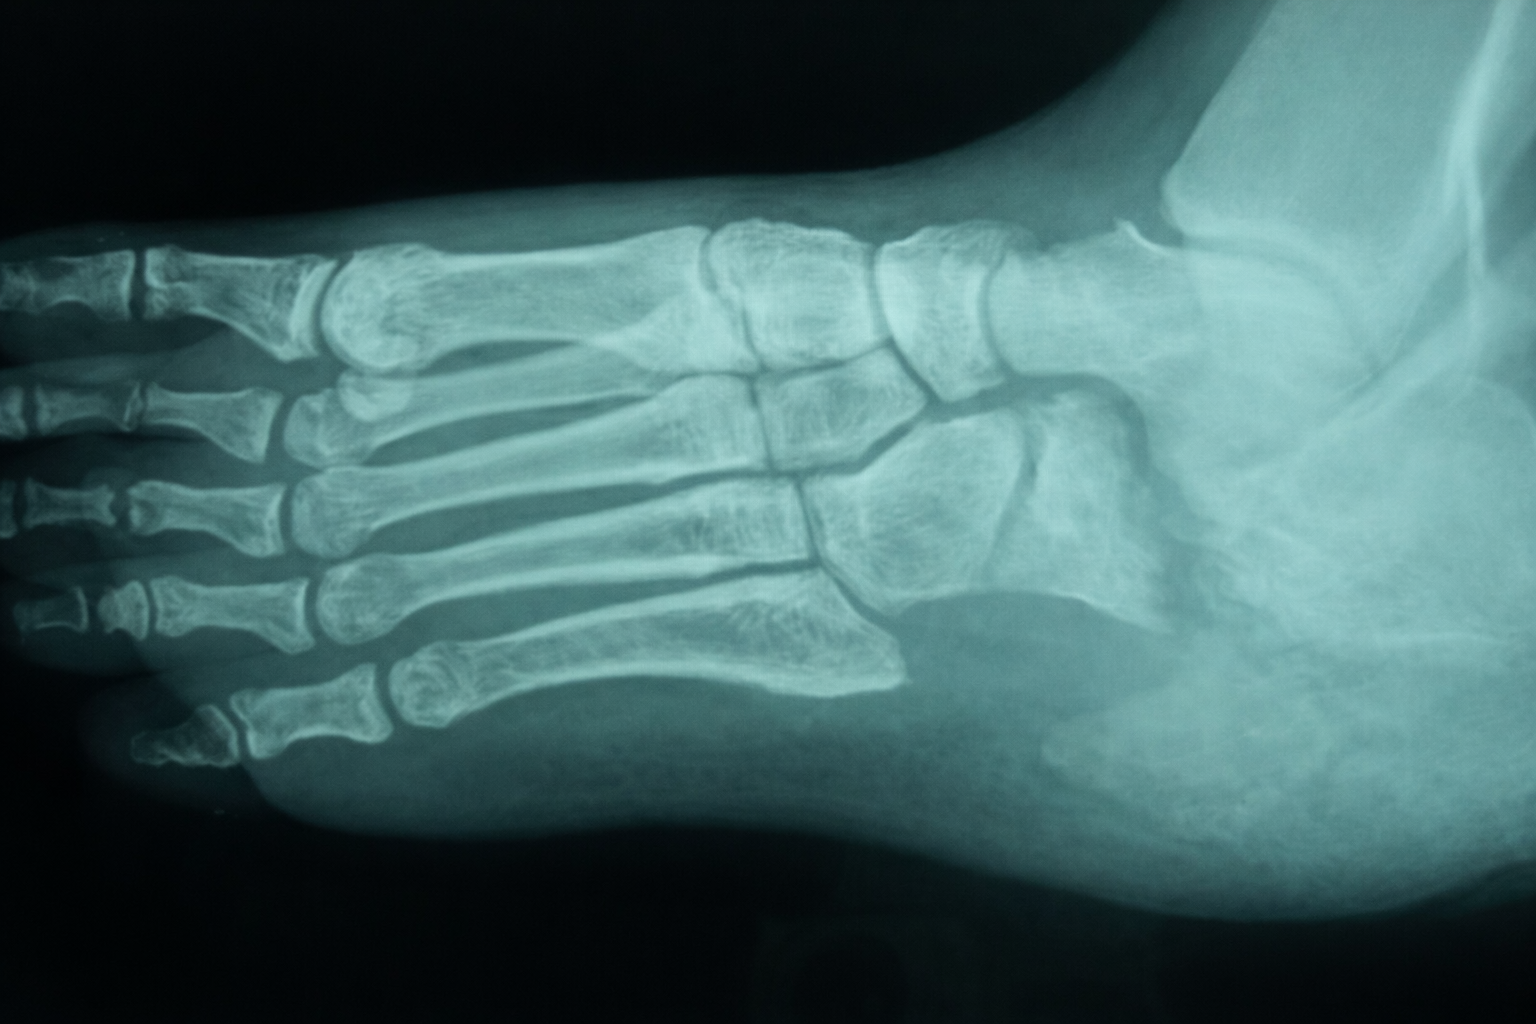

Figure 2showing radiograph of a patient with osteomyelitis of calcaneum. This is type 3-C diabetic foot osteomyelitis according to Amit Jain’s classification.

Diabetic foot osteomyelitis continues to be one of the most common challenging entities to diagnose and manage accurately10. Osteomyelitis and diabetic foot infection are common entities with serious complications that can result in lower extremity amputation11. Osteomyelitis should always be considered when the ulcer fails to heal1. Infact, osteomyelitis in diabetic foot occurs via contiguous spread from an adjacent infected wound in 94% of the cases2. In our study, all cases of osteomyelitis were due to local pathology, with 90.48% cases having underlying ulcer. Such cases belong to type 3 diabetic foot complications12. Various classifications have been suggested for osteomyelitis in general of which Waldogel and Cierny- Mader are the two most commonly employed classification13, 14. Amit Jain’s classification for diabetic foot osteomyelitis15, 16 is a new classification specific for diabetic foot osteomyelitis. Around 90% of diabetic foot ulcers are known to occur in forefoot, 1.5% in the midfoot and 4.5% in the calcaneus1. Hence, forefoot is the most likely involved anatomical region for osteomyelitis. Around 7-8% of the cases have calcaneal osteomyelitis17, 18. In our study, 57.14% had forefoot osteomyelitis [type 1 diabetic foot

osteomyelitis] and 23.81% had type 3 osteomyelitis which involved calcaneum. The possible reason for such a high incidence of hindfoot osteomyelitis compared to that in the literature is due to the fact that most physicians avoid treating calcaneal osteomyelitis and refer to higher centre or specialist surgeon for further management as the results with hindfoot osteomyelitis are not quite favourable. Diagnosis of osteomyelitis can sometimes be difficult in diabetic foot, especially in early cases11, 19, where x rays may not show any changes. In such cases magnetic resonance imaging {MRI} or bone scintigraphy may be required. MRI has been shown to have the highest sensitivity and specificity [>90%] for diagnosing osteomyelitis2. The only problem occurs when one has to distinguish osteomyelitis from charcot foot5. In our study, 9.52% of cases had charcot foot along with osteomyelitis. In one study6, 64.3% of patients with osteomyelitis had underlying peripheral vascular disease whereas in our study, none of the patient had peripheral vascular disease. It is quite obvious due to the fact that majority of diabetic foot patients in India suffer from neuropathy and infection16, 20. Management of diabetic foot osteomyelitis varies from centre to centre and region to region5. Some specialist believes in management of osteomyelitis with antibiotics alone whereas some believe in early surgical treatment5. Conservative surgery1, 6 is defined as procedure in which no amputation of any part of the foot is undertaken and includes debridement of non viable/infected tissues and bones. Major amputation includes below knee and above knee amputation. In literature, major amputation from osteomyelitis ranges from 8 – 25%4, 5, 6, 11. In our study, 33.33% had major amputation whereas only 28.57% had conservative surgical approach. There was no mortality in our series. This study on osteomyelitis using Amit Jain’s classification osteomyelitis provides a better insight on osteomyelitis and for diabetic foot henceforth the classification would help to form a better communication tool. This new classification is one of the component of Amit Jain’s Principle and Practice of diabetic foot consisting of newer concepts in diabetic foot like typings, grading and scoring the diabetic foot complications to improvise and standardize the practice of diabetic foot around the world12, 16, 21, 22, 23.